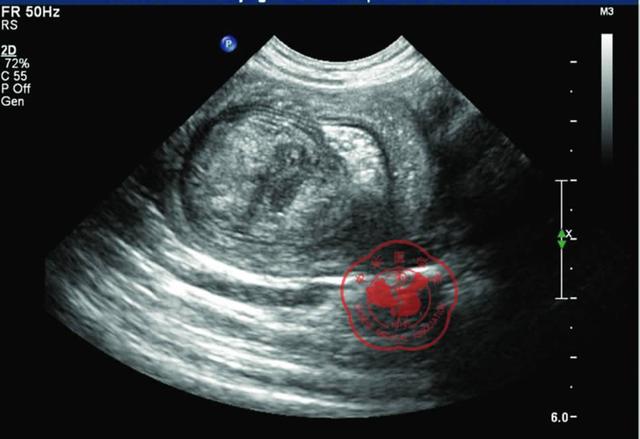

超声所见:回肠横切面,可探及“同心圆”征象,套入头端可见一中等回声结节